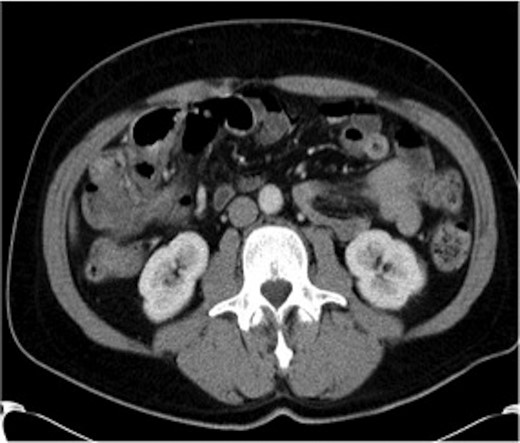

Haemoglobin was 12.6 g/dl and a WCC of 8.3 × 109/l. Other remarkable laboratory tests included a CRP of 19 mg/l. Urinalysis was normal. The AXR revealed a grossly distended large bowel. A CT scan of the abdomen revealed that the rectum, sigmoid and descending colon were collapsed with an apparent calibre change within the transverse colon with no mass lesion (Fig. 3).

CT of the abdomen (Case 2) showing a calibre change within the transverse colon with no mass lesion.